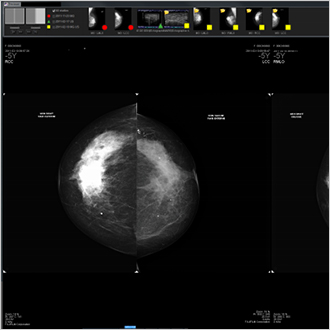

TM-Mammo

La soluzione TM-Mammo è stata specificamente concepita per le esigenze di memorizzazione, distribuzione e diagnosi dell'imaging digitale mammografico nell'ambito dei reparti di senologia. Il visore TM-Mammo permette un facile confronto tra le immagini storiche del paziente (per tutti i tipi di condizioni), con visualizzazione di sequenze specifiche. La tomosintesi è stata integrata nelle sequenze di visualizzazione.